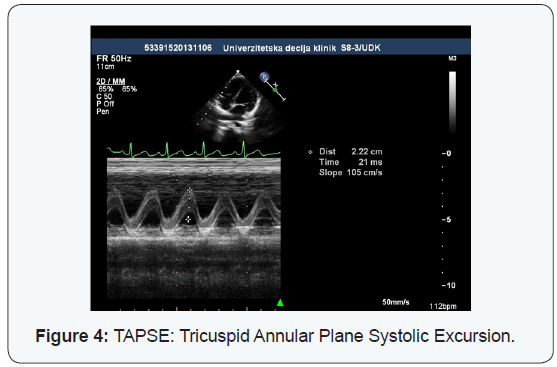

TAPSE (Tricuspid Annular Pulse Systolic Excursion)

The moving of the tricuspid valve annulus, between the end of diastole to the end of systole chamber, is a very good indicator of right ventricular systolic function and it correlates well with the parameters of systolic function obtained by right diagnostic cardiac catheterization and using magnetic resonance imaging. TAPSE however, represents only the impact of the right ventricular entrance on systolic function, while the contribution of outflow tract is assessed on the basis of the shortening fraction of that part of the right ventricle. The assessment of right ventricular systolic function of the standard methods used in the left ventricle such as ejection fraction and shortening fraction, is harder to do, because of its irregular geometry, trabecular walls and retrosternal position. This problem is particularly seen in children with congenital heart disease where, a wide range of abnormalities in the structure, shape and position of the right ventricle, is present.

In healthy children included in our study, TAPSE average value was 22.4 ± 3.7 mm, which, due to the most common age of the children in our study, fits in with the reference values that Nunez Gil [12] got in his study. In our study, lower limit value of TAPSE that you get when you subtract the mean value of 2 SD, would come to 15 mm. By examining the healthy children, Nunez Gil [12] come to the value of TAPSE which he characterized as a reference for certain ages. The mean value in all age groups was 17.09 ± 5.09 mm. TAPSE values ranged from 10.56 ± 3.96 mm in newborns, to 20.95 ± 6.54 mm in children aged 13-18 years. There were no significant differences between the sexes. Body surface area showed a strong positive correlation with the values TAPSE, while heart rate showed a negative correlation with TAPSE. TAPSE values, in relation to the body surface area (BSA), differed at different average values BSA in certain age groups and it was to 13.17 mm / m2 at an average BSA of 1.59 m2. In the neonatal age 5th percentile TAPSE was 7.8 mm, while in the age of children older than 5 years, 5th percentile TAPSE was 15 mm. All of these values obtained in healthy children contribute to proper interpretation and clinical applicability of the values TAPSE in children with various heart diseases.

Perhaps the most important use of TAPSE is in children with pulmonary arterial hypertension. Koestenberger [13] cites a number of studies that have shown a significant reduction in the value of TAPSE in patients with pulmonary hypertension compared to healthy children. As a determinant of progressive damage to the right ventricle systolic function, TAPSE value 2 SD below the normal value for age, was defined. With the speed of systolic tricuspid annular motion (Sm), TAPSE becomes the method of choice for routine assessment of right ventricular systolic function in the monitoring of patients with pulmonary arterial hypertension.